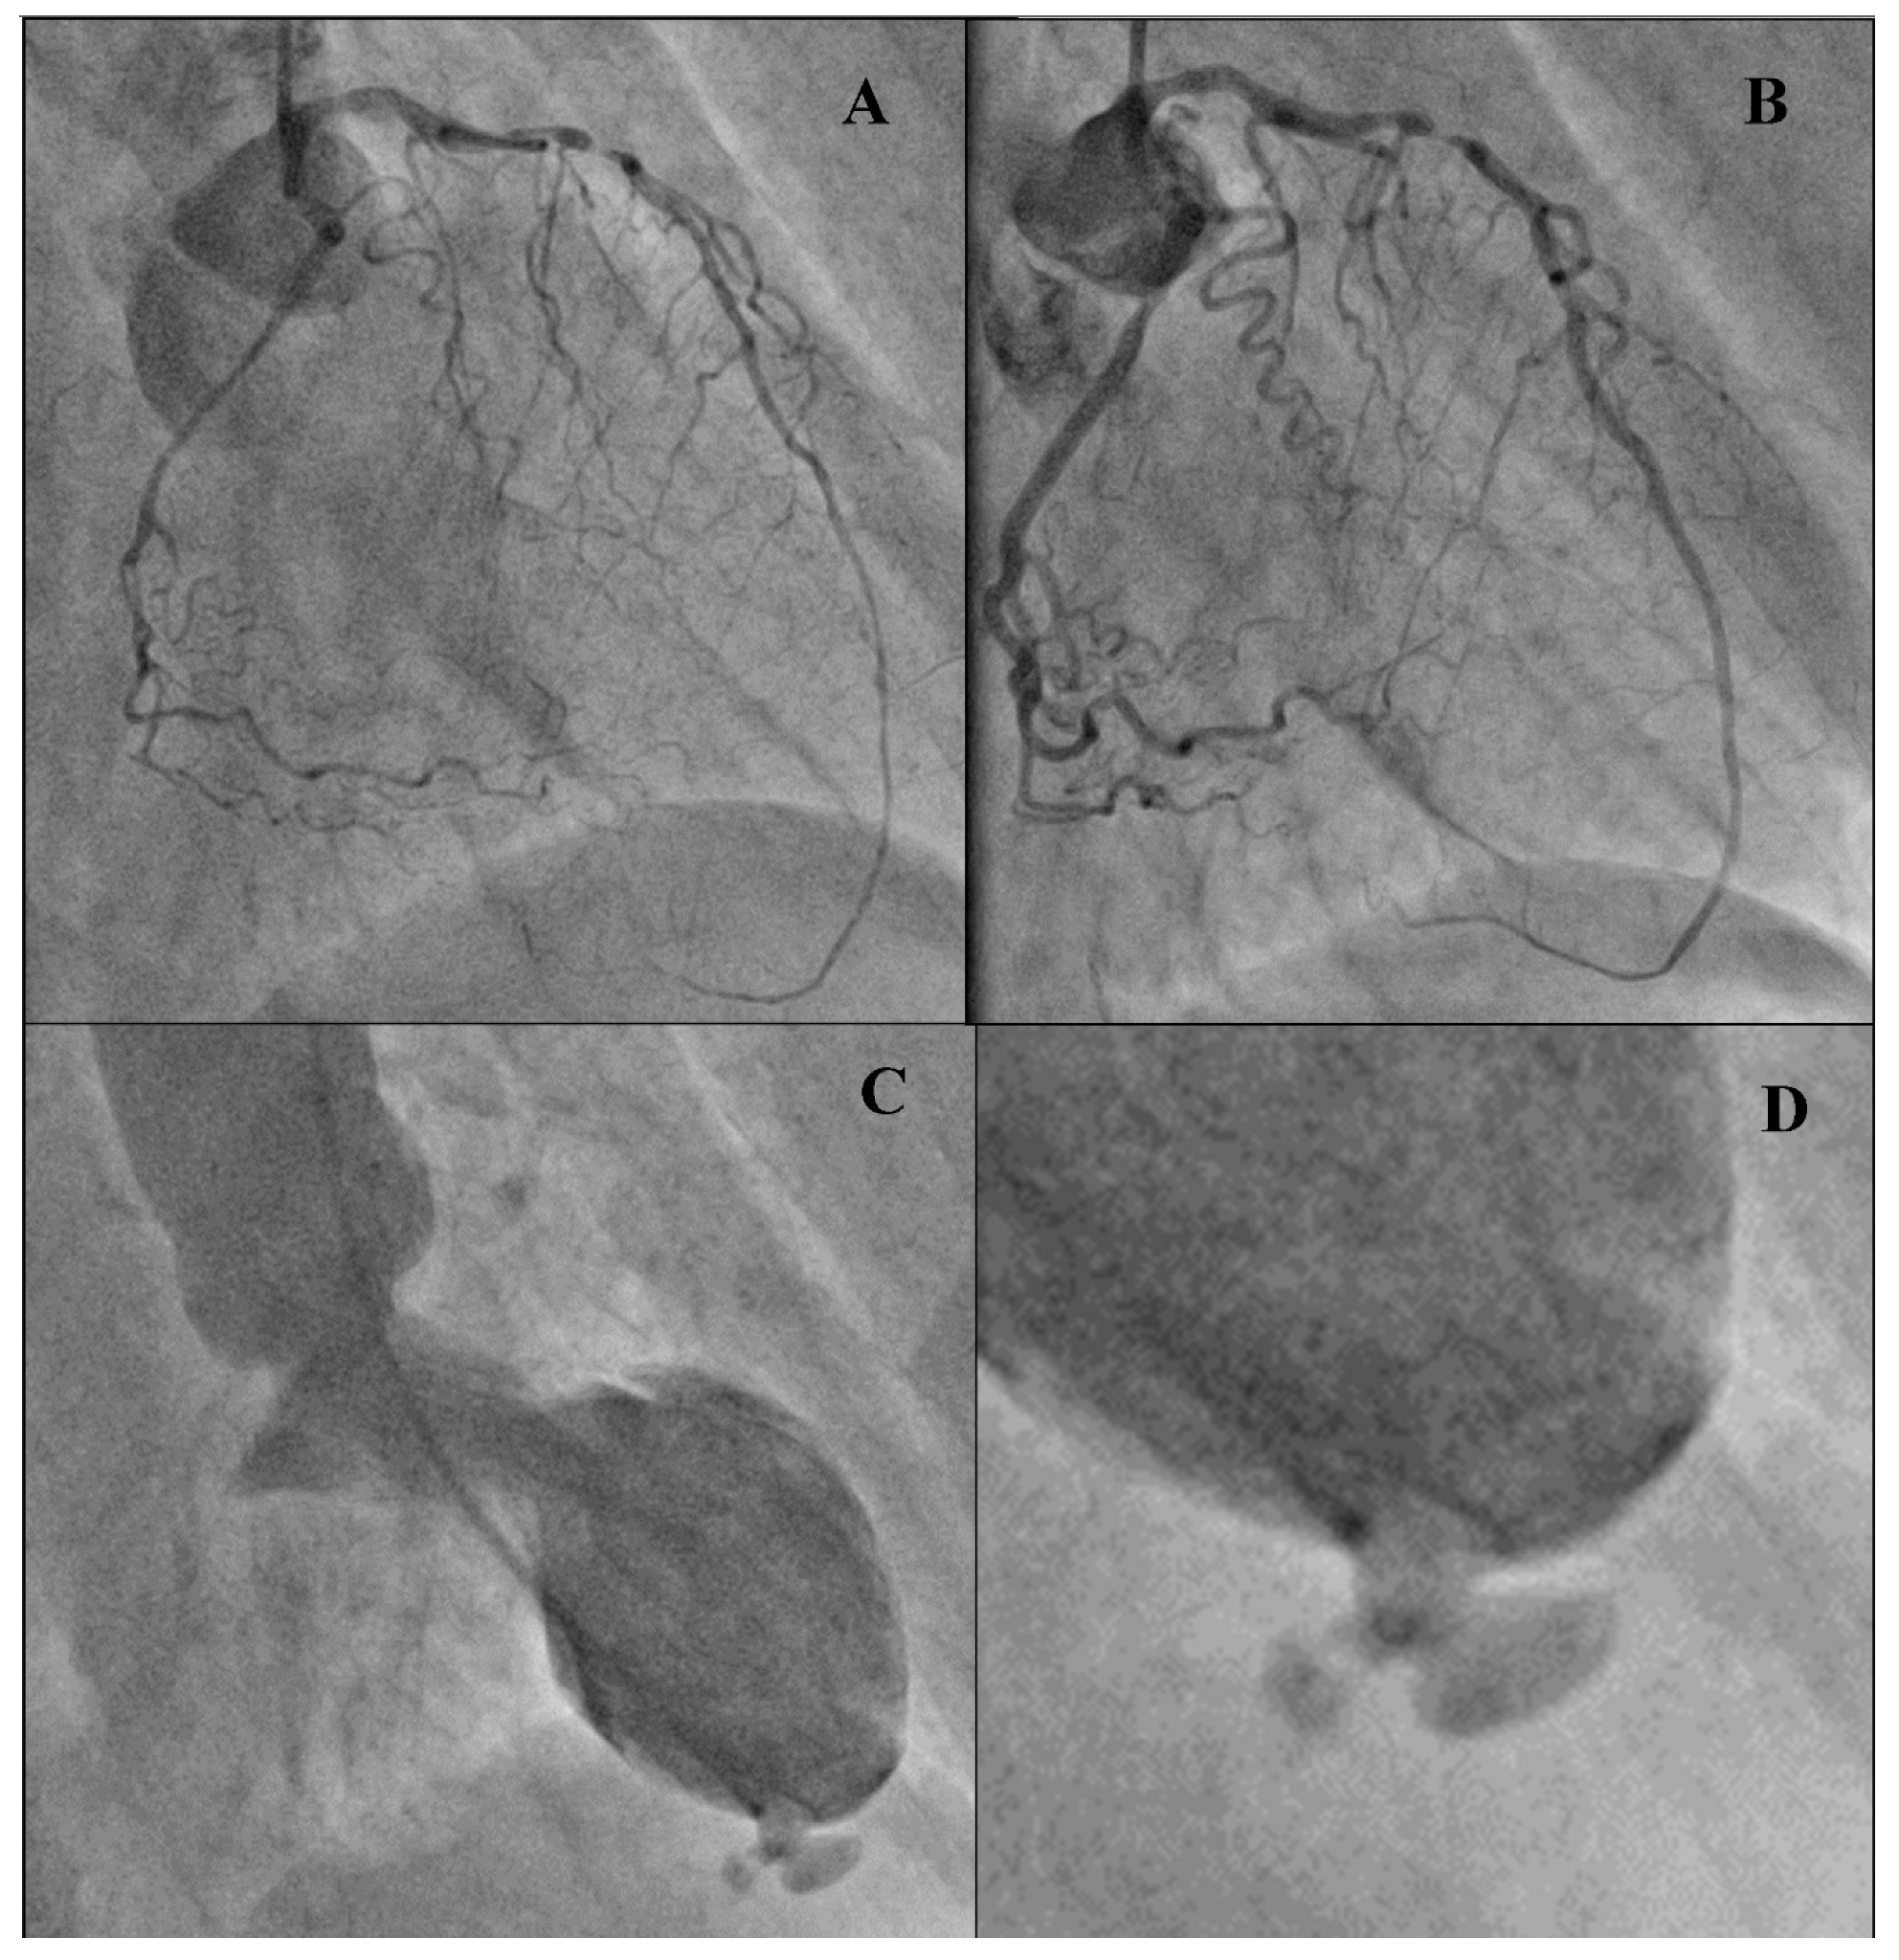

Left Ventricular Rupture as a Complication of Anterior Wall Myocardial Infarction on Computed Tomography Angiography and Ventriculography